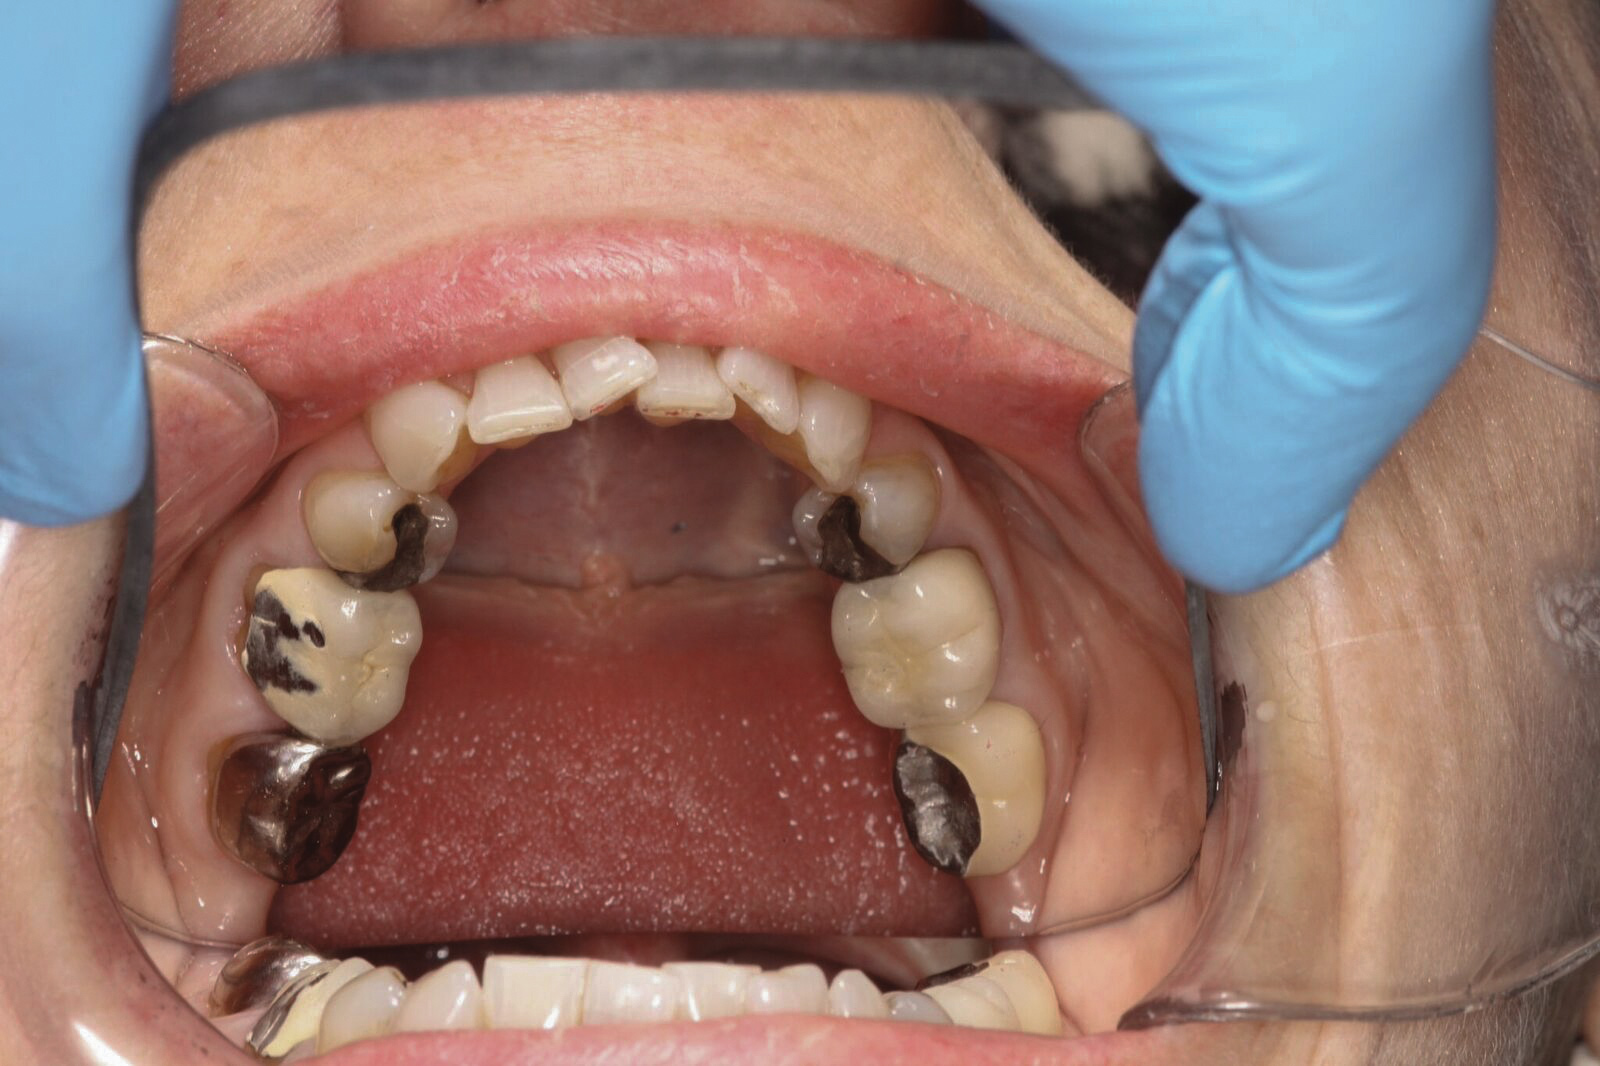

Dental sleep medicine (DSM) is a field in dentistry dedicated to the use and research of oral appliance therapy for the management of snoring and OSA. Oral appliance therapy is a noninvasive alternative to PAP therapy. Oral appliances fabricated by dentists with training in dental sleep medicine are commonly used to reposition the lower jaw forward to increase upper airway patency. Dental professionals have been recognized as being part of the multidisciplinary therapeutic team for the management of OSA because of their prime position of constant examination of the oropharyngeal areas. There are several oropharyngeal features contributing to the development of a narrow upper airway. These features are easily identifiable during a routine dental appointment, such as a large and scalloped tongue (Figure 1), narrow maxilla (Figure 2), small mandible (Figure 3), and retrognathic mandible (Figure 4). Combining clinical history intake, oropharyngeal examination, and the use of validated screening questionnaires, such as the STOP-Bang, dentists can screen for signs and symptoms of OSA and make recommendations for further diagnostic testing.

(4.) Lateral x-ray showing a retrognathic and entrapped mandible.

Figure 4